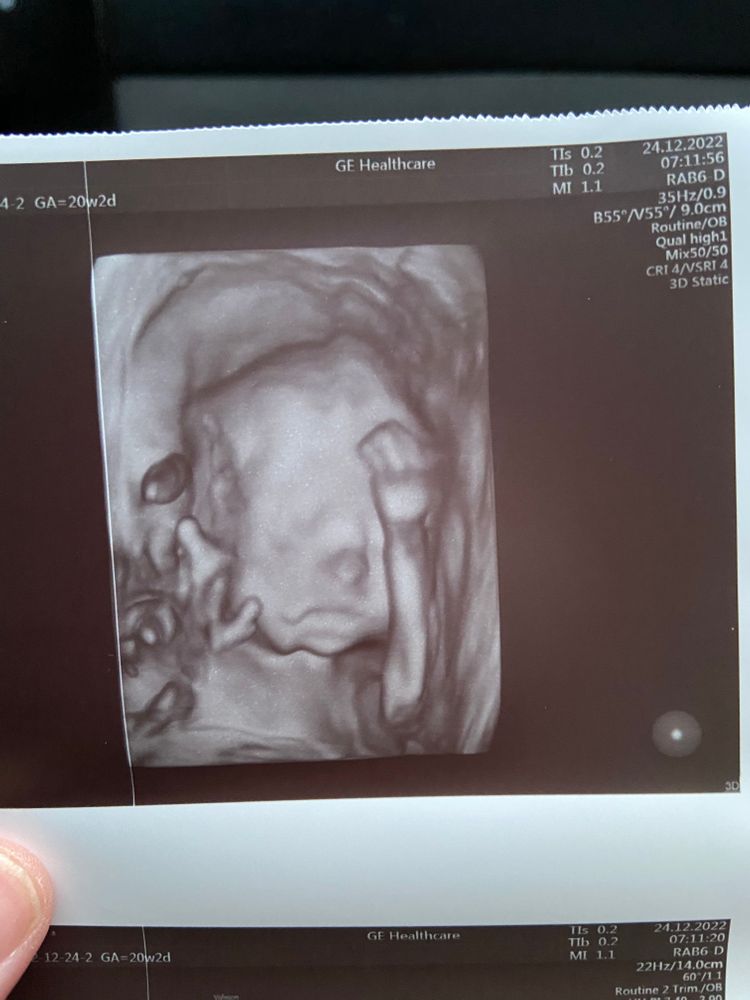

20 недель и 2 дня второй скрининг

сохраню на память. Ведь это был особенный день. Мы впервые на узи увидели нашу девочку в 3д… в этот день дети старшие выступали на отчетном концерте по бальным танцам и нам надо было успеть съездить на узи и приехать на концерт:). На узи ездил муж, дети готовились к выступлению.